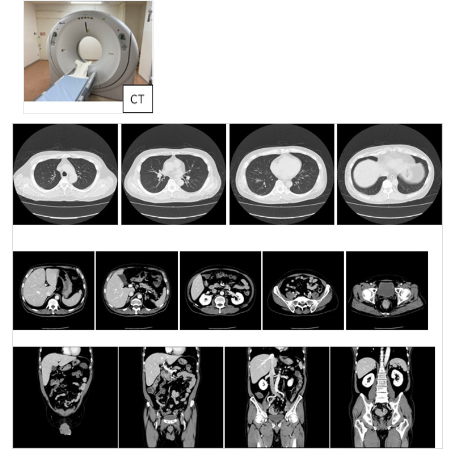

マルチスライス 64列CT |

キャノンメディカル | Aquilion CX |

◆実際の撮影写真